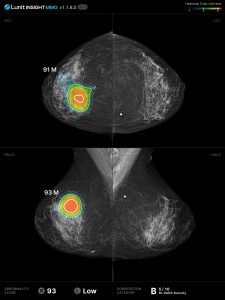

Na imagem abaixo podemos ver como é uma leitura realizada por IA de um exame de mamografia de uma paciente com câncer de mama.

mamografia com leitura por inteligência artificial